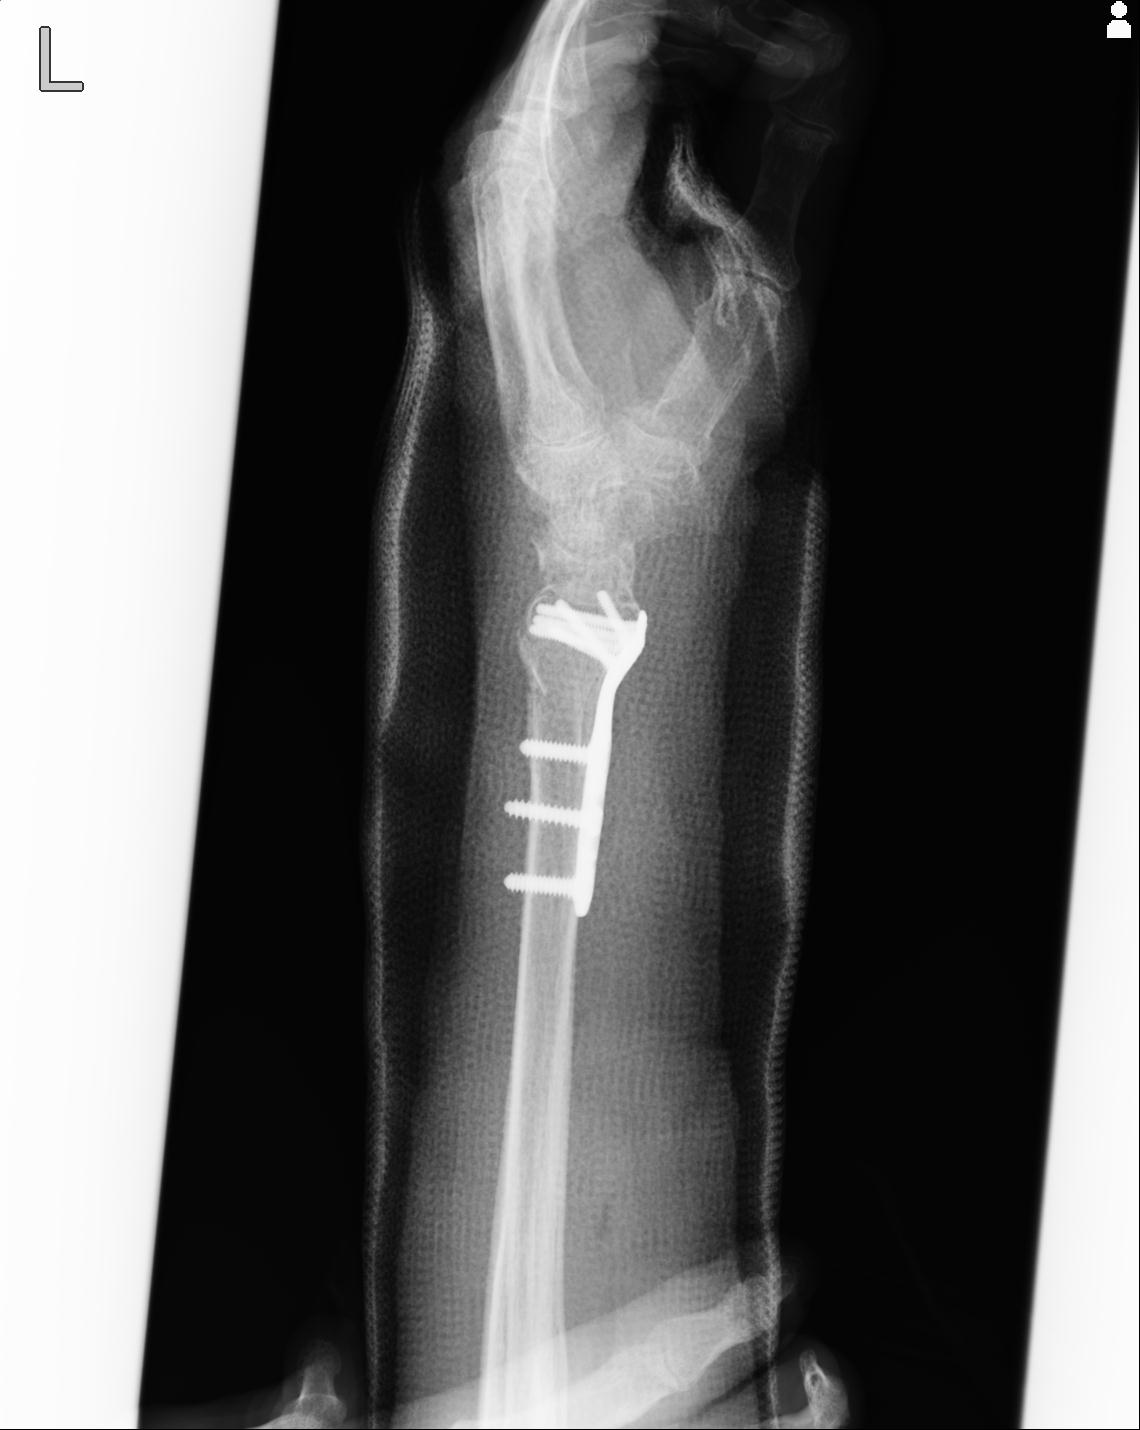

110211 1/6 1/8 左前腕 4R 15歳男性 橈骨骨幹部骨折